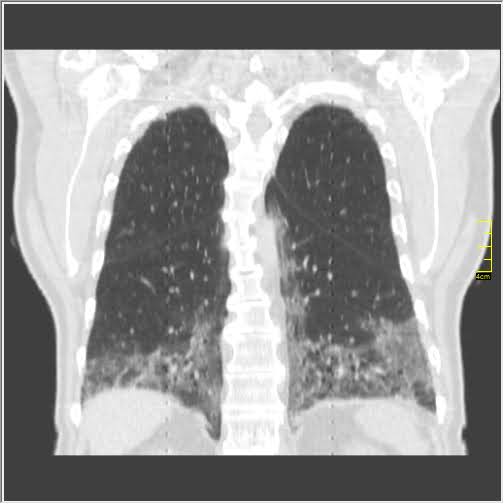

Foto: Aleksandar Ivković Foto: Aleksandar Ivković Foto: Aleksandar Ivković Zastrašujući snimci skenera pluća od 1. do 15. dana kovida autor: Božica Luković Zdravlje 26. nov. 2020. 12:33 > 26. nov. 2020. 13:35 0 Podeli vest: Kovid 19 je nepredvidiva bolest koja u razmaku od par dana može iz blage da preraste u opasnu po život. Kako koronvirus utiče na pluća iz dana u dan, pokazao je na snimcima CT skenera srpski radiolog Aleksandar Ivković. Podeli vest: Oglas Lekar iz Niša na svom blogu "Ljudi i ostale laži" redovno piše o svim važnim temama u vezi sa koronavirusom, a sada je odlučio da prikaže CT skenere pluća osobe obolele od kovida 19.Objasio je šta lekari tačno prate kada su u pitanju snimci pluća, ali i kako se te stavke menjaju kako bolest napreduje.Njegovu objavu prenosimo u celosti."Vraćam se na svoju usku struku (da ne bude da se mešam u tuđu). Kompjuterizovana tomografija, skener ili CT je metoda pregleda koja je superiorna kod zapaljenskih bolesti pluća. Kod kovida 19 se pokazala kao nezamenjiva u diferencijaciji u odnosu na ostale bolesti. Tačnost nalaza na plućima je visoka. Šta mi to možemo videti i kako tumačimo? Stvari koje pratimo su:- Ground glass konsolidacije (GGO).To su one bele "mrlje" na snimcima koje su karakteristične za ovu bolest. Nazivaju se "ground glass" svuda. Izgledaju kao da se taj deo pluća gleda kroz mlečno staklo, kao neka vrsta mikromozaika. Foto: Aleksandar Ivković | Foto: Aleksandar Ivković - Crazy paving.To su linearna zadebljanja koja se nekada vide u ground glass konsolidacijama. Ona nastaju kasnije, ne javljaju se pre GGO. Neko ih opisuje kao da pijani majstori slažu pločice. Na slikama se to vidi kao nepravilna zadebljanja unutar GGO, složena bez ikakvog reda. Foto: Aleksandar Ivković | Foto: Aleksandar Ivković - Vaskularne dilatacije. Dolazi do zapaljenskog procesa krvnih sudova i/ili do zastoja tako da su nam na snimcima krvni sudovi "deblji". Foto: Aleksandar Ivković | Foto: Aleksandar Ivković - Trakcione bronhiektazije. To su proširenja vazdušnog prostora (ali ne onog koji učestvuje u disanju) koja nastaju kada stradaju alveole i proširuje se prostor između njih. Foto: Aleksandar Ivković | Foto: Aleksandar Ivković - Arhitektonske distorzije. Pojava traka blizu pleure koje nastaju propadanja plućnog tkiva i nastanka fibroznog. Foto: Aleksandar Ivković | Foto: Aleksandar Ivković Svaki od ovih znaka se može javiti i kod drugih bolesti ali svi zajedno su specifični za kovid-19Da bi objasnili stanje koristimo Severity Score. On služi za procenu ozbiljnosti bolesti. Pluća se sastoje od pet lobusa. Procenjuje se svaki pojedinačno ocenama od 0 do 5. To znači da se skor kreće od 0 do 25.0 - znači da nema GGO konsolidacija1- znači da je manje od 5% tog lobusa zahvaćeno2 - znači da je zahvaćeno od 5 do 25% tog lobusa3 - znači da je zahvaćeno 26 do 50% tog lobusa4 - znači da je zahvaćeno 51 do 75% tog lobusa5 - znači da je zahvaćeno više od 75% tog lobusa Na CT razlikujemo 4 faze (najčešće ali nije decidirano tako) Rana faza (0 do 4. dan) - pojedinačne GGO, neka crazy paving, nizak skor Foto: Aleksandar Ivković | Foto: Aleksandar Ivković Progresivna faza (5. do 8. dan) - povećanje broja GGO i crazy paving Foto: Aleksandar Ivković | Foto: Aleksandar Ivković Pik faza (10. do 13. dan) - javljaju se konsolidacije pluća, to znači da veliki delovi pluća izgledaju kao velike bele površine a označavaju delove pluća koji su masa koja koja je u celini zahvaćena zapaljenskim procesom. Foto: Aleksandar Ivković | Foto: Aleksandar Ivković Faza rezolucije (posle 14. dana) - vraćanje delova pluća u normalu ili smrt Foto: Aleksandar Ivković | Foto: Aleksandar Ivković Iskustveno smo došli do skora 15 koji predstavlja neku granicu između verovatno dobrog i verovatno lošeg ishoda. Samo tumačenje zavisi od faze bolesti. Naš nalaz je samo deo procene i ne menja laboratorijske i pulmološke, kao ni ostale. Svaki nalaz zajedno daje ukupnu sliku bolesti. Foto: Aleksandar Ivković | Foto: Aleksandar Ivković Nalaz je u88% slučajeva sa obe strane,88% ground glass,80% posteriorno,79% multilobularno,76% periferno i30% konsolidacijeTo je posao radiologa, to je moj posao. Sasvim sigurno je da bez ovih slika lečenje ne bi bilo lako. Pacijente delimo na lake - one koji nemaju tegobe, teške - one koji imaju zahvaćeno do 50% pluća i kritične a to su oni kod kojih je više od 50% zahvaćeno", piše dr Ivković.***Bonus video:https://www.youtube.com/watch?v=fYeYlhqeD5cPratite nas i na društvenim mrežama:FacebookTwitterInstagram Revolucija iz Niša: Test na koronu koji predviđa tok bolesti Zdravlje 0 Tekst naučnika koji ruši sve zavere o koroni - i daje nadu Zdravlje 0 72 sata pakla od kad su me zabolela pluća u kovid Srbiji Zdravlje 0 aleksandar ivković ct skener koronavirus kovid-19 pluća Pratite nas na društvenim mrežama: Koje je tvoje mišljenje o ovoj temi? Učestvuj u diskusiji ili pročitaj komentare Budite prvi koji će ostaviti komentar Pošalji komentar Pročitaj komentare (0)